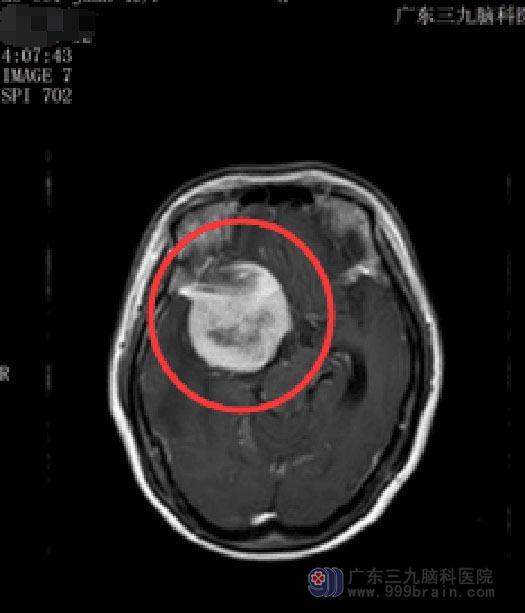

近期她再次出现相同症状,四肢乏力也愈发严重,这回小娟有点紧张了。在广东三九脑科医院头颅MR检查显示“右侧鞍旁占位性病变,考虑脑膜瘤,并右侧海绵窦受累,邻近脑实质受压、水肿”,此时,她的右眼已经完全失明。

结合患者症状、体征、头颅MR检查,考虑小娟病史较长,病情进行缓慢,查体出现定位体征,肿瘤在CT上表现为等密度或稍高密度,有占位效应,肿瘤边界清楚,呈圆形、类圆形或不规则分叶形,多数瘤周存在一环形或弧形的低信号区,强化或增强后呈均匀明显强化,考虑脑膜瘤可能性大。